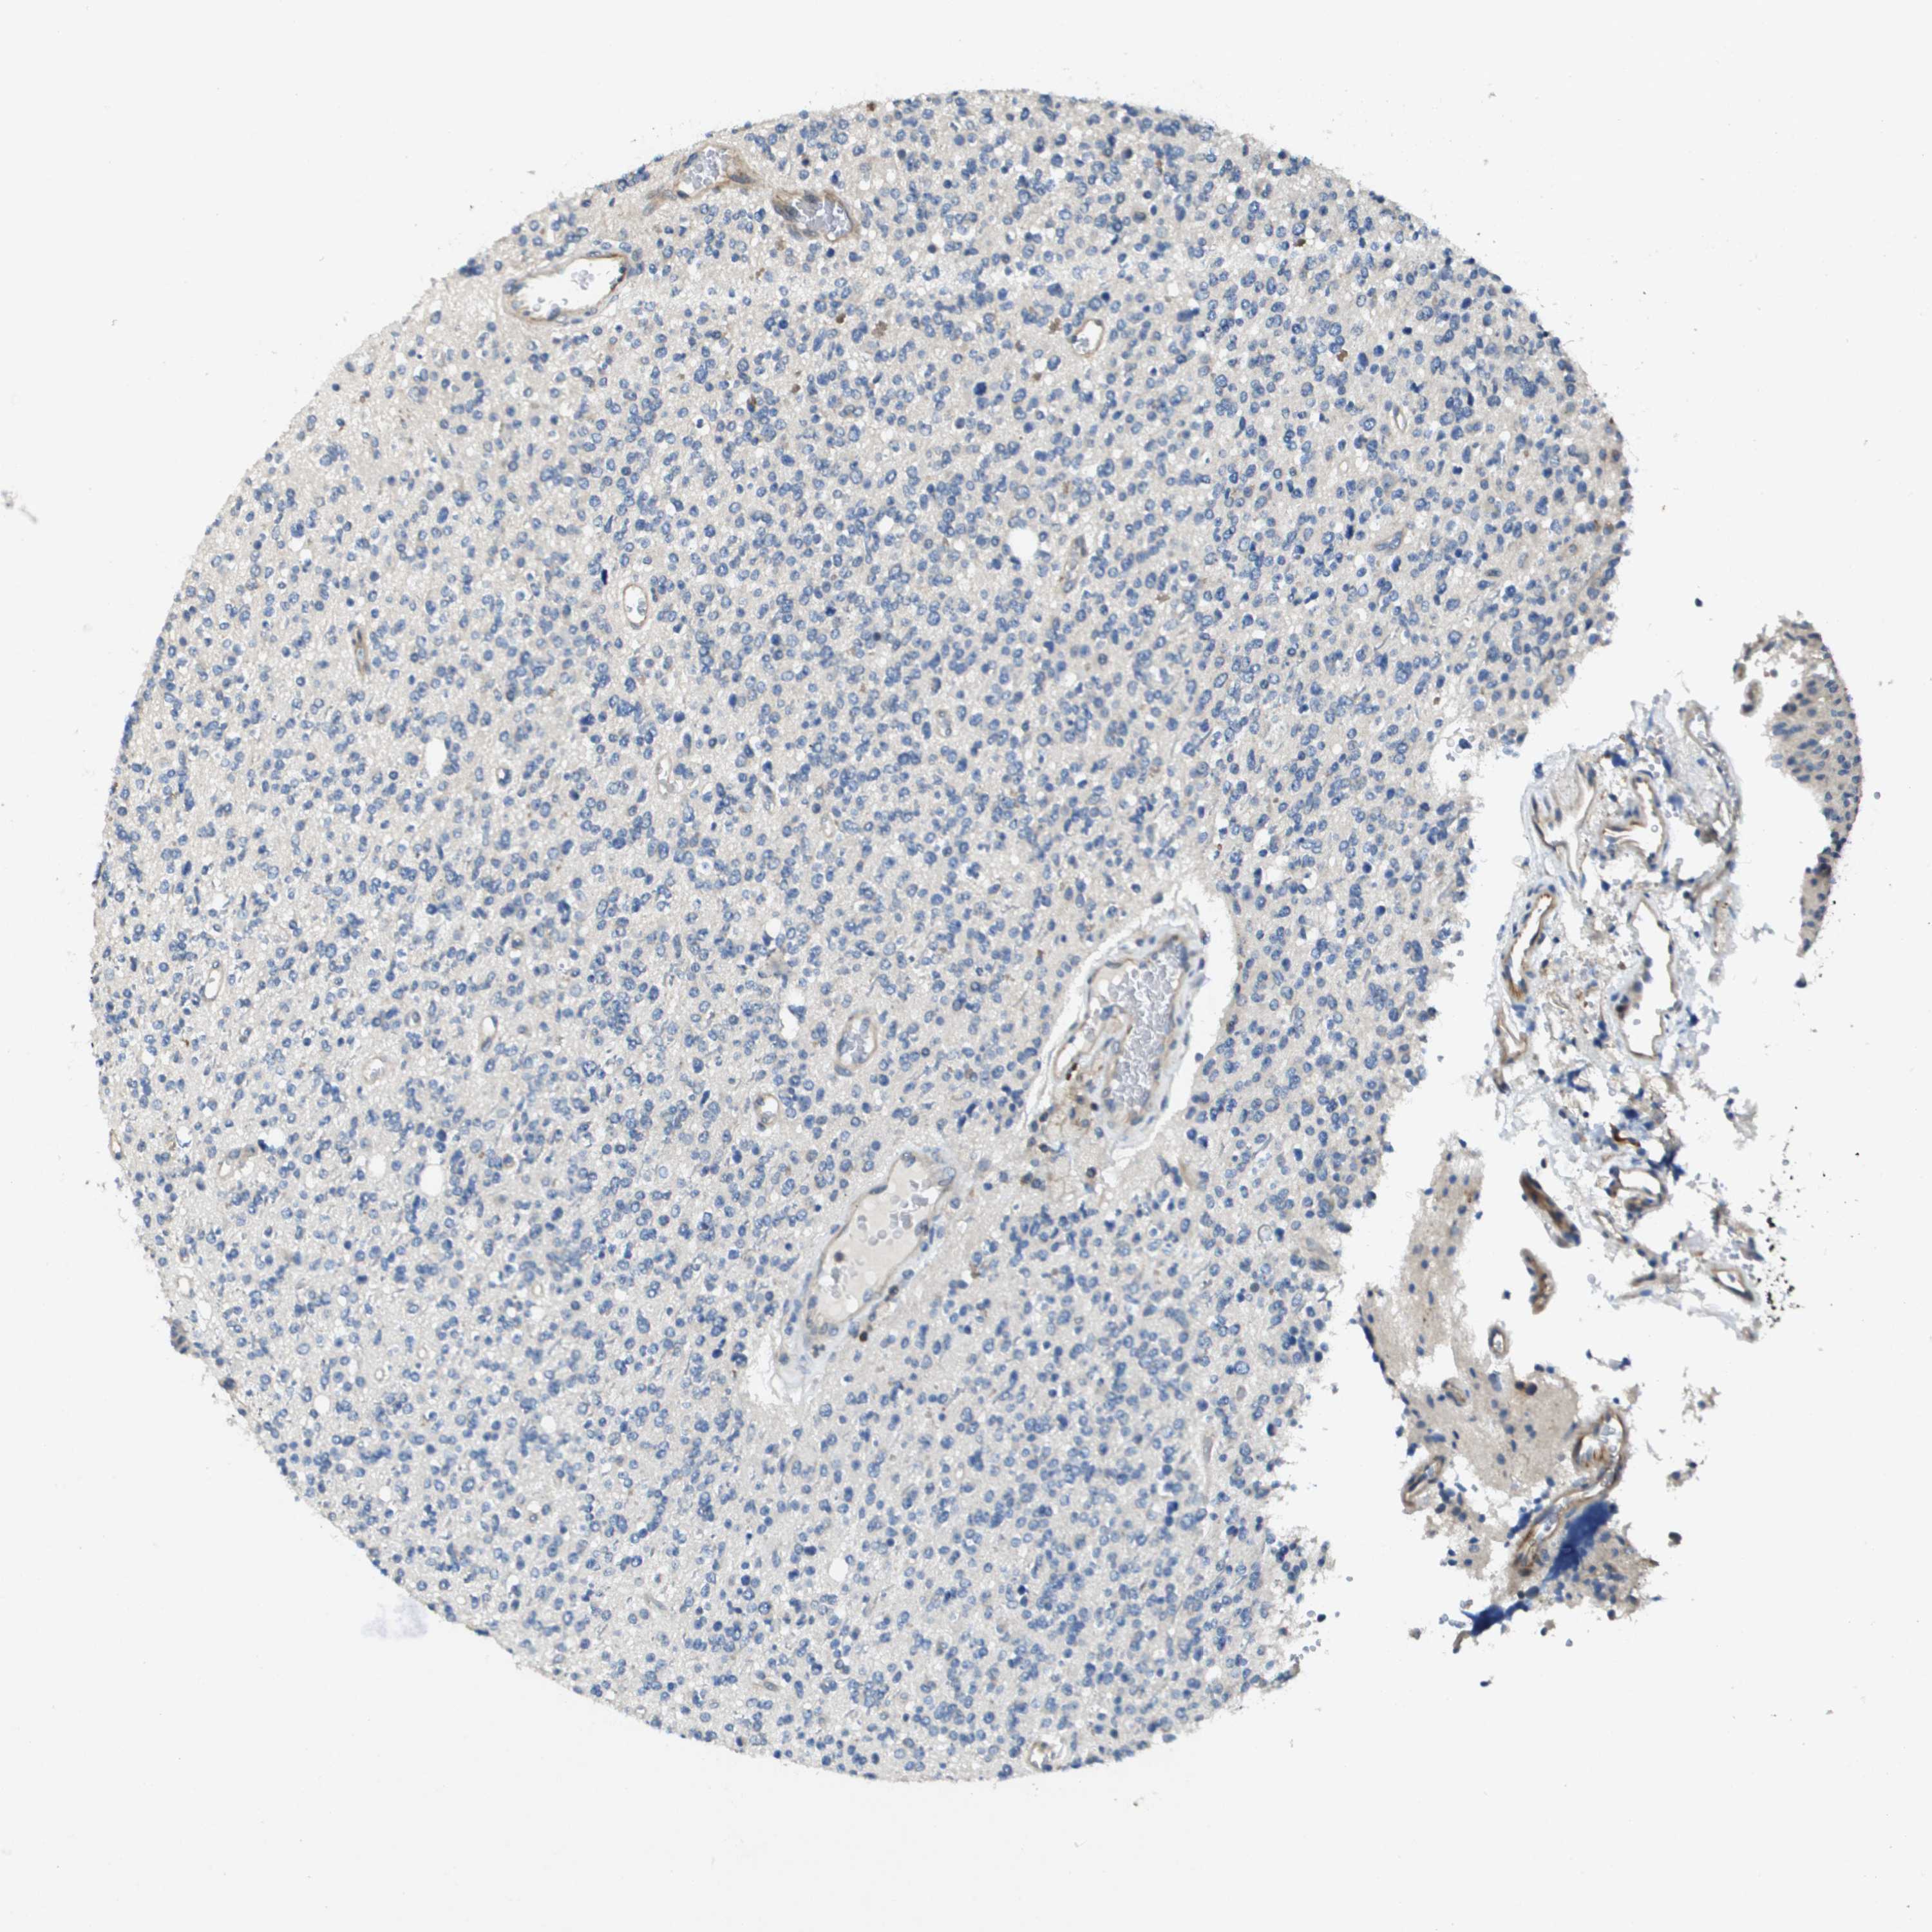

GLIOMA - Protein expressioni

A mouse-over function shows sample information and annotation data. Click on an image to view it in a full screen mode. Samples can be filtered based on level of antibody staining by selecting one or several of the following categories: high, medium, low and not detected. The assay and annotation is described here.

Note that samples used for immunohistochemistry by the Human Protein Atlas do not correspond to samples in the TCGA dataset.

Antibody stainingi

Antibody staining in the annotated cell types in the current human tissue is reported as not detected, low, medium, or high, based on conventional immunohistochemistry profiling in selected tissues. This score is based on the combination of the staining intensity and fraction of stained cells.

Each image is clickable and will lead to virtual microscopy that enables deeper exploration of all samples and also displays staining intensity scores, fraction scores and subcellular localization as well as patient and tissue information for each sample.

Antibody HPA017293

Staining

High

Medium

Low

Not detected

Intensity

Strong

Moderate

Weak

Negative

Quantity

>75%

75%-25%

<25%

None

Location

Nuclear

Cytoplasmic/membranous

Cytoplasmic/membranous,nuclear

Glioma, malignant, High grade

Glioma, malignant, Low grade